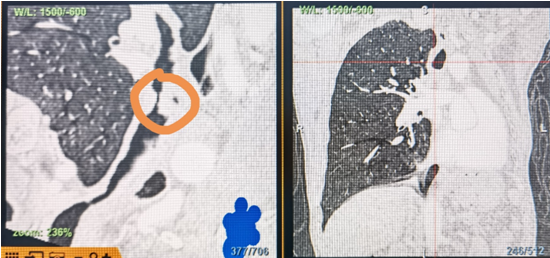

時(shí)間就是生命!了解患者病情后,歐陽(yáng)海峰立刻啟動(dòng)氣道梗阻緊急救治通道,協(xié)調(diào)院前轉(zhuǎn)運(yùn),急診快速入院流程。凌晨患者入院胸部CT顯示,現(xiàn)存唯一的呼吸通道在右主支氣管處,狹窄處僅約3毫米,患者命懸一線!

運(yùn)用呼吸介入技術(shù),軟硬鏡結(jié)合快速開通氣道,是患者目前唯一可行的治療方案,手術(shù)刻不容緩!但存在麻醉后氣道完全塌陷閉合、大出血、窒息等巨大風(fēng)險(xiǎn)。患者此前接連轉(zhuǎn)診3家醫(yī)院,均建議保守支持治療或轉(zhuǎn)院。歐陽(yáng)海峰詳細(xì)了解患者病史,全面評(píng)估影像檢查結(jié)果后,決定盡快進(jìn)行手術(shù),組織醫(yī)護(hù)團(tuán)隊(duì)對(duì)患者進(jìn)行持續(xù)密切監(jiān)測(cè),充分保障其術(shù)前安全。

患者入院第二天,在麻醉手術(shù)中心全力配合下,歐陽(yáng)海峰帶領(lǐng)呼吸介入團(tuán)隊(duì),歷時(shí)40分鐘快速置入硬質(zhì)支氣管鏡、鏟切腫瘤,并順利植入全覆膜TTS支氣管金屬支架?;颊邭舛贪Y狀即刻緩解,為患者贏得了寶貴的后續(xù)治療機(jī)會(huì)。